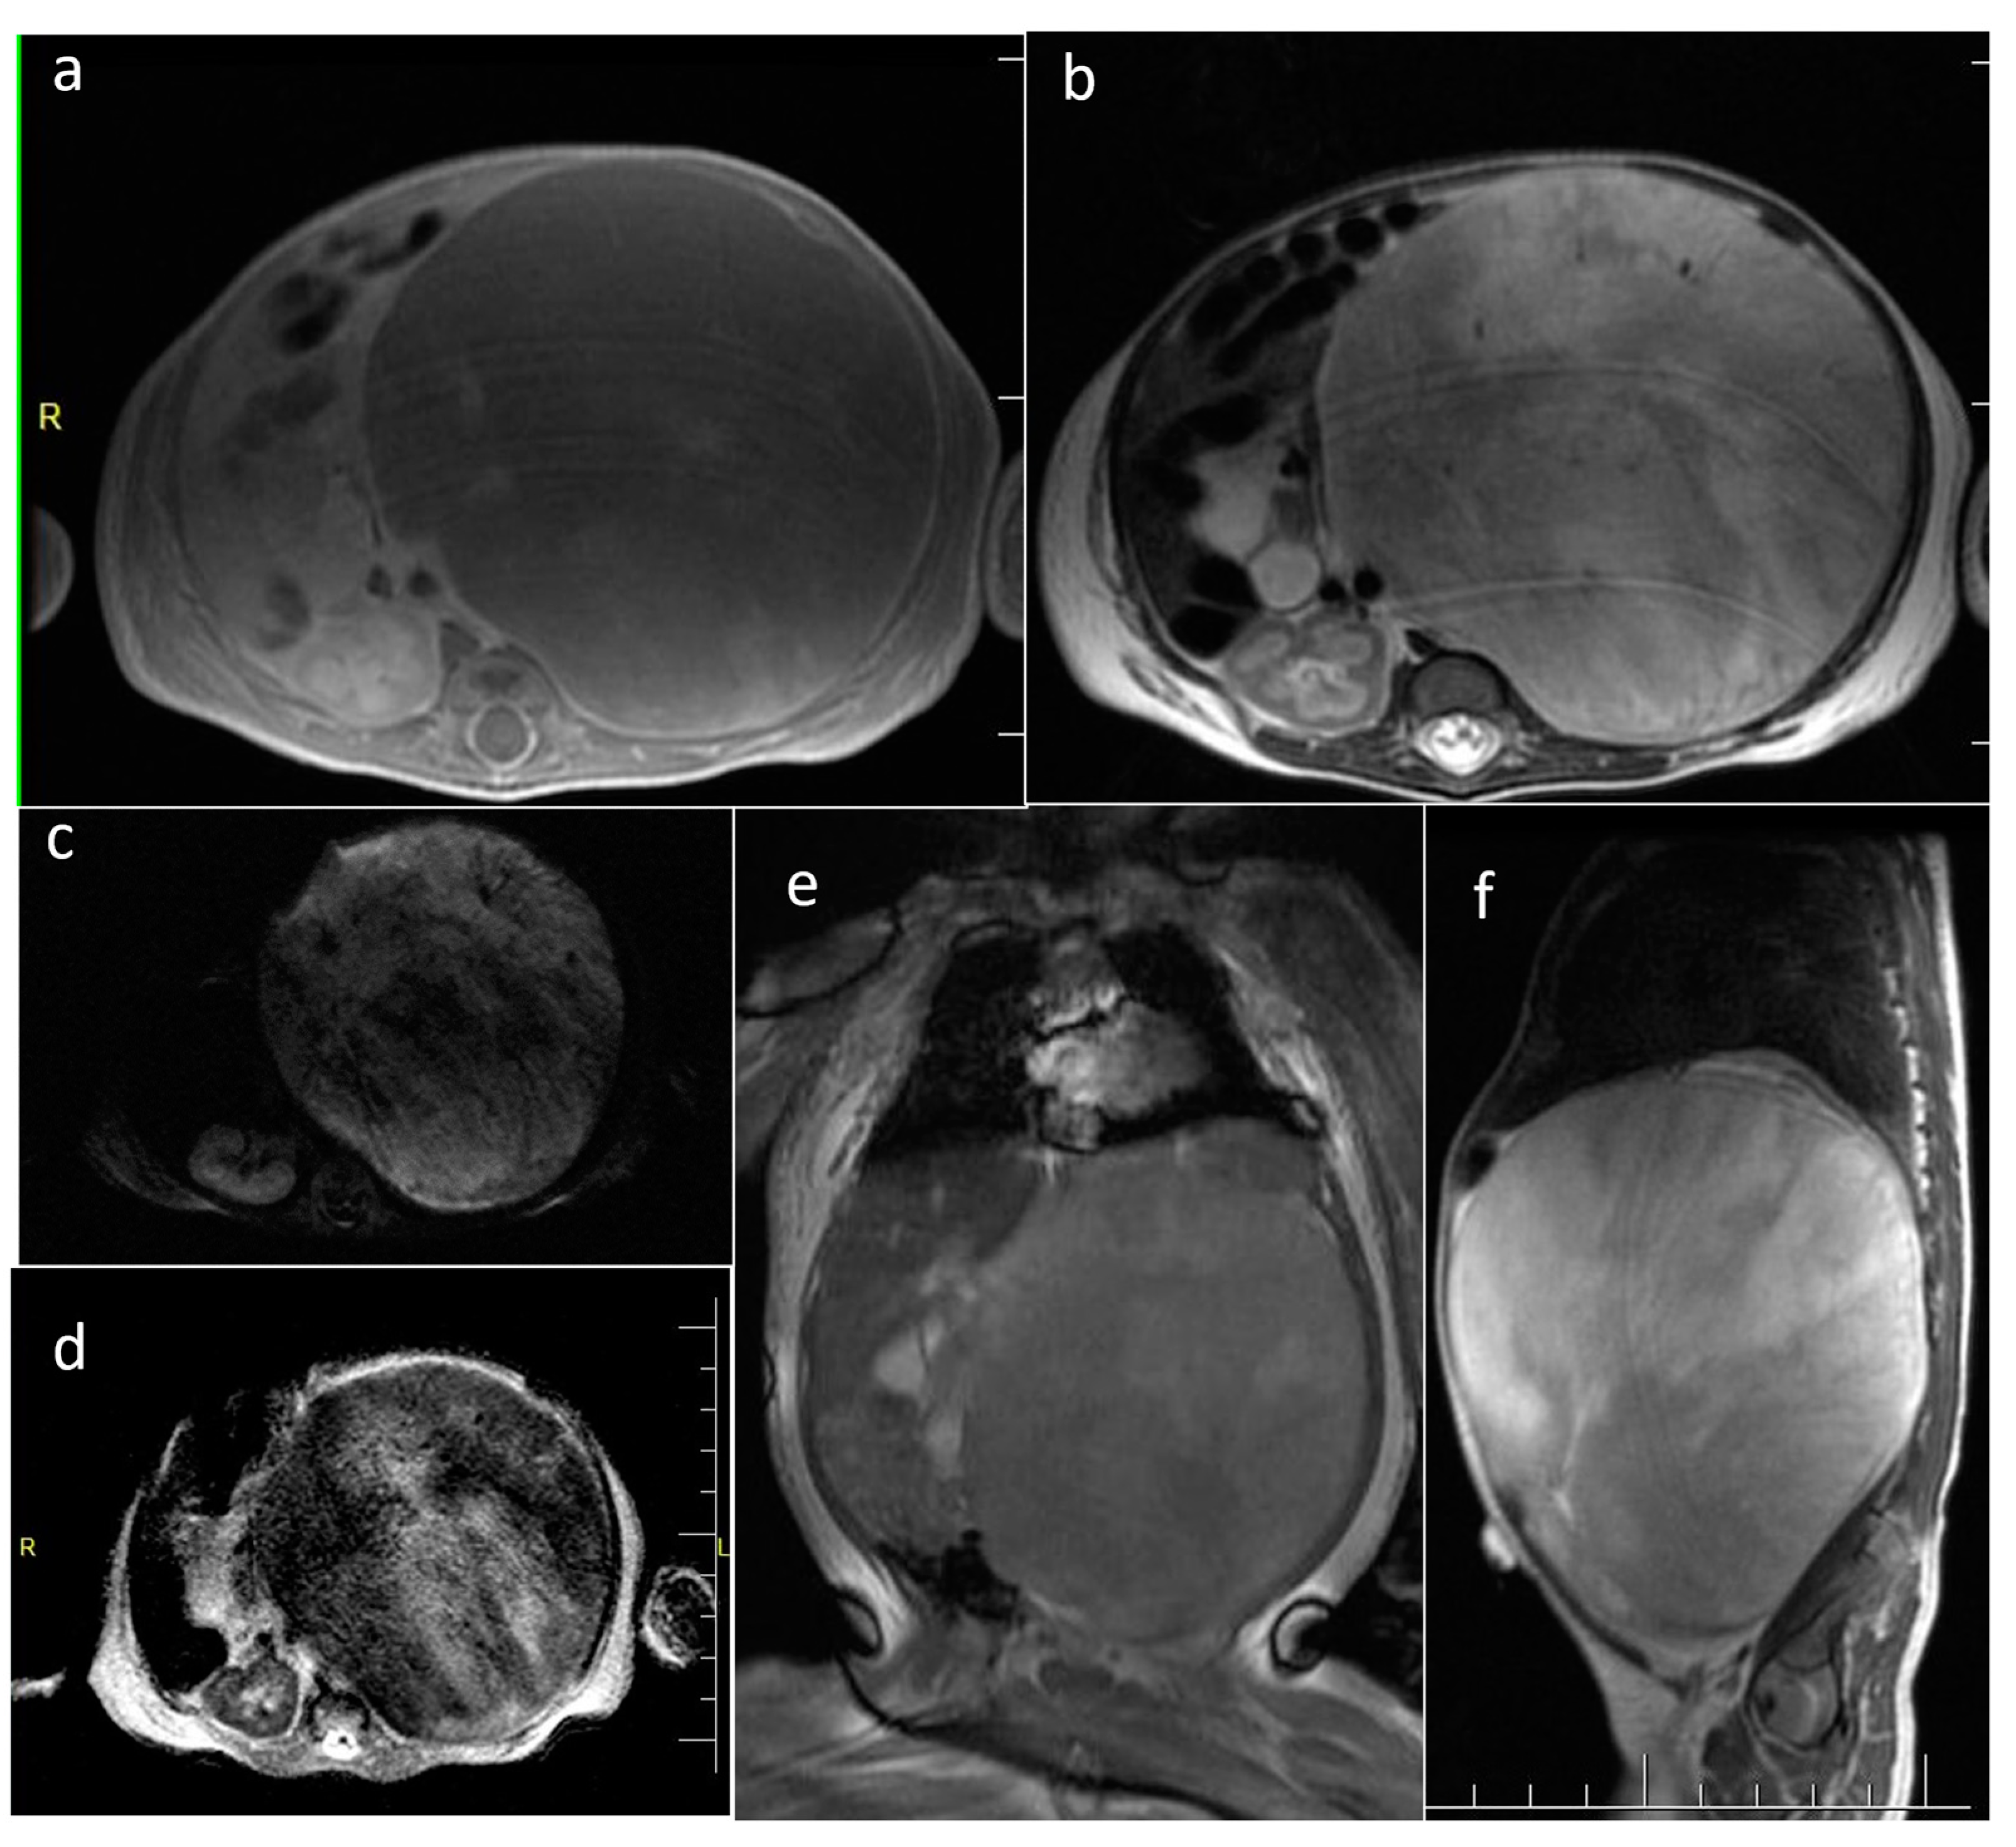

| Infantile myofibroma | left buttock and thigh, pelvis | 1 | 461 | yes (1056) | Solid | No | yes |

| Juvenile xanthogranuloma (JXG) | abdomen | 1 | irregular shape | no | Cystic | N/A | yes |

| Blue rubber bleb nevus syndrome/Bean syndrome (BRBNS) | abdomen, tongue | 2 | 141 [124–158] | no | Solid | 1/2 | N/A |